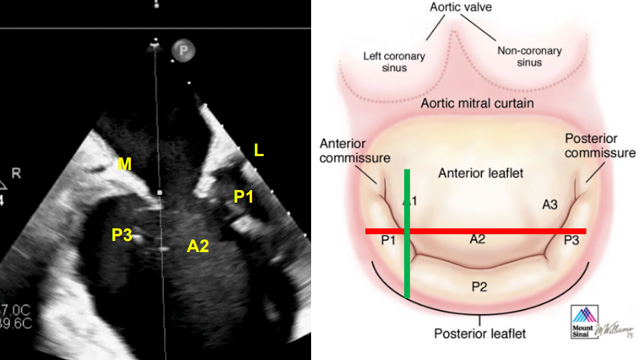

M-TEER difficult situation: small mitral valves, P2 prolapse & leaflet degeneration

08 Feb 2025 – From PCR Tokyo Valves 2025

Explore a series of challenging cases in Mitral Transcatheter Edge-to-Edge Repair (M-TEER), highlighting the versatility and adaptability of this technique. Discover how M-TEER can be successfully applied in patients with extremely small mitral valves, P2 prolapse supported by chordae from the posterior papillary muscle, wide prolapse...